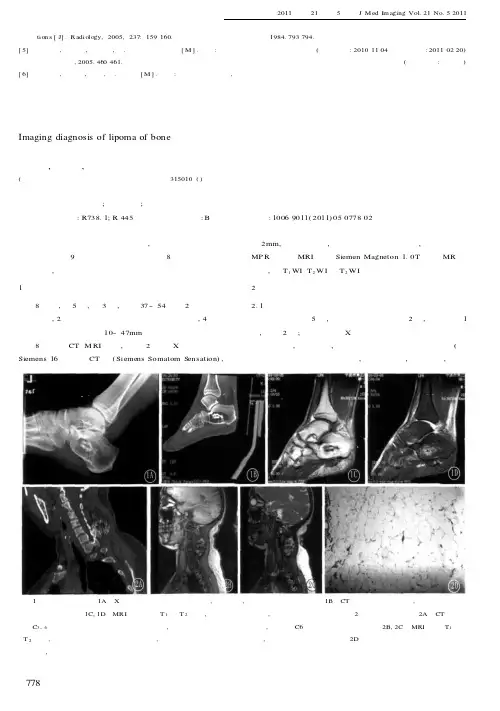

结果8例患者全部瘤灶界清,边缘光滑,无分叶,数目3~11个,平均5个,长径1mm~38cm,平均12cm,CT及MRI均表现为脂肪密度影,CT值-75~-130Hu,平均-119Hu,MRI表现为与皮下脂肪信号一致,即T1高、T2中高信号,STIR为低信号。

胼胝体区14个(压部11个,体部3个),脑池区13个(分布于环池、四叠体池、脉络丛、大脑大静脉池、桥小脑脚池等),丘脑4个,松果体区3个,脑干2个,大脑半球凸面3个,侧脑室三角区脉络膜丛1个。

CT发现伴环线状钙化2个,MR未显示钙化信号。

CT及MR发现的伴发病:脑梗塞3例,胼胝体发育不良3例,鼻窦炎3例,透明隔间腔2例。

结果颅内脂肪瘤CT表现为脂肪密度影,CT值约为-20~-120 HU,平均为-56.3 HU,MRI表现为T1WI和T2WI图像上均呈高信号,与皮下脂肪类似。

脂肪瘤主要分布在中线及附近,其中11例位于胼胝体区;6例合并有其他颅脑发育异常,其中4例为胼胝体发育异常。

CT➢单发或多发边缘光整的极低密度区,ct值-120~ -80 hu,密度均匀。

MRI➢脂肪瘤信号具有特征性➢T1WI呈高信号,T2WI呈中高信号,边缘清楚。

➢在所有序列中均与皮下脂肪信号相同,可含等信号的纤维间隔。

➢在脂肪抑制序列上,T1WI的高信号、T2WI的中高信号可被抑制。

❖前臂可见不规则形软组织肿块。

❖T1WI高信号。

❖T2 WI高信号,内部可见纤维分隔。